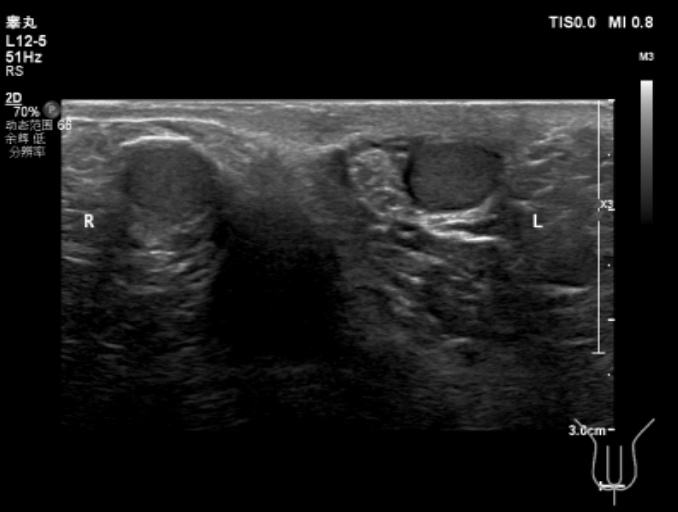

#4检查有条不紊地进行中,相关结果陆续回复,真相也逐渐露出了水面......● 小林的甲状腺功能未见明显异常,皮质醇、ACTH 节律基本正常,最重要的性激素结果显示:促黄体激素(LH)和睾酮水平都明显低于正常值,FSH 位于正常值下限。图 3:性激素六项结果 来源:作者提供● 睾丸彩超提示:双侧睾丸体积明显偏小。图 4:睾丸彩超报告 来源:作者提供● 垂体 MRI 平扫 + 增强显示:垂体未见明显异常。图 5:垂体 MRI 增强来源:作者提供当这些检查结果摆在面前时,我基本上可以肯定之前的判断是正确的。接下来,距离确诊就剩最后一个步骤了——曲普瑞林兴奋试验:给小林肌肉注射曲普瑞林 100 ug,60 分钟后测得 LH 为 2.08 mIU/mL(< 4 mIU/mL),提示性腺轴未启动。曲普瑞林试验最后排除了体质性青春发育延迟,我们最终给小林明确了诊断:特发性低促性腺激素性性腺功能减退症(IHH)。